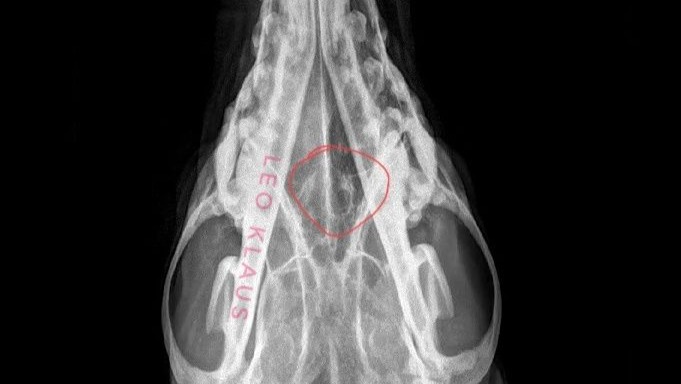

He went in on December 4th, was sedated, and got an X-ray done on his head and chest. This told us nothing aside from yes - there is a hole in his bone. There's no mass or tumor, there's no fuzziness on the edges of the hole, and his lungs look good. My vet, who has been seeing Sage since I got him, doesn't believe it to be cancer, though he also said unilateral nosebleeds are rarely not cancer. But, X-rays can only pick up so much in terms of other possibilities - Could it be a foreign body like a foxtail? A fungal infection like Aspergillosis? Neither of those show up on X-ray.